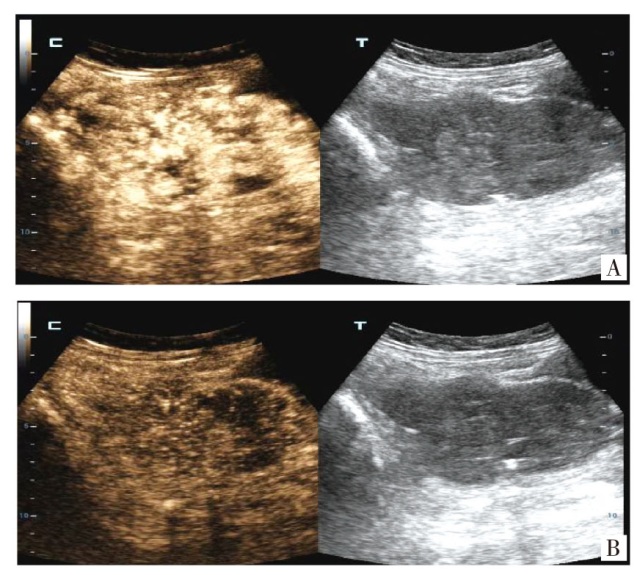

报告1例原发于宫颈的未分化子宫肉瘤病例。患者因绝经7年,阴道出血1周就诊,妇科检查触及宫颈9 cm大小的肿物,影像学检查提示宫颈巨大肿物及盆腔积液,未见明显肿大的淋巴结。遂行经腹全子宫切除术+双侧输卵管卵巢切除术,术后病理活检及免疫组织化学检查提示低级别未分化子宫肉瘤。术后患者拒绝放化疗,未定期复查。半年后再次因阴道出血,下腹部胀痛就诊,影像学提示阴道残端占位性病变,考虑肿瘤复发可能,遂行经导管髂内动脉栓塞术+髂动脉造影+动脉注射化疗药物(顺铂60 mg+表柔比星30 mg)。2个月后又因间断阴道出血在外院化疗1次。定期随访9个月,期间未行治疗,间断阴道出血。后失访。

A case of primary undifferentiated uterine sarcoma of the cervix is reported. The patient presented for medical consultation due to vaginal bleeding for 1 week after 7 years of menopause. A 9 cm mass in the cervix was detected during a gynecological examination. Imaging studies indicated a huge cervical mass and pelvic effusion, with no obvious enlarged lymph nodes. Subsequently, an abdominal total hysterectomy and bilateral salpingo-oophorectomy were performed. Postoperative pathological biopsy and immunohistochemistry suggested low-grade undifferentiated uterine sarcoma. After the operation, the patient refused radiotherapy and chemotherapy and did not undergo regular follow-up. Six months later, the patient presented again with vaginal bleeding and lower abdominal distension and pain. Imaging showed a space-occupying lesion at the vaginal stump, and tumor recurrence was considered possible. Therefore, transcatheter internal iliac artery embolization, iliac artery angiography and intra-arterial injection of chemotherapy drugs (cisplatin 60 mg + epirubicin 30 mg) were carried out. Two months later, the patient received chemotherapy once at another hospital due to intermittent vaginal bleeding. The patient was followed up regularly for 9 months, during which no treatment was administered, and intermittent vaginal bleeding occurred. The patient was then lost to follow-up.